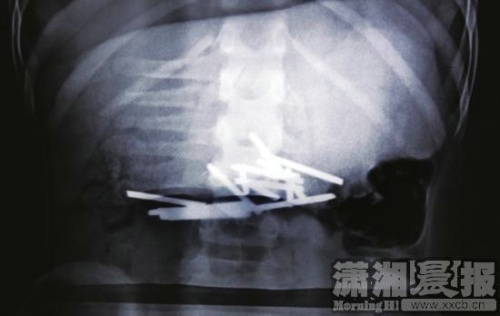

2、57岁的李连深被孙子小文(化名)的老师告知:吞了一个铁钉。结果老师陪同他们去医院检查,在肚子里发现了12根铁钉。小文说是5个同学欺负他,逼他吞下这些钉子。小文班主任肖老师在班上调查后发现,并非如小文所说是班上同学强迫他吞钉子,而是他自己吞下去的。肖老师坦言,小文在班上很调皮,有时还会吃纸。这一点,得到了小文奶奶的证实。现在小文经过X光检查,肠道位置有12根钉子,医生要对他保守治疗,争取排出钉子。如果不能,只能手术了。